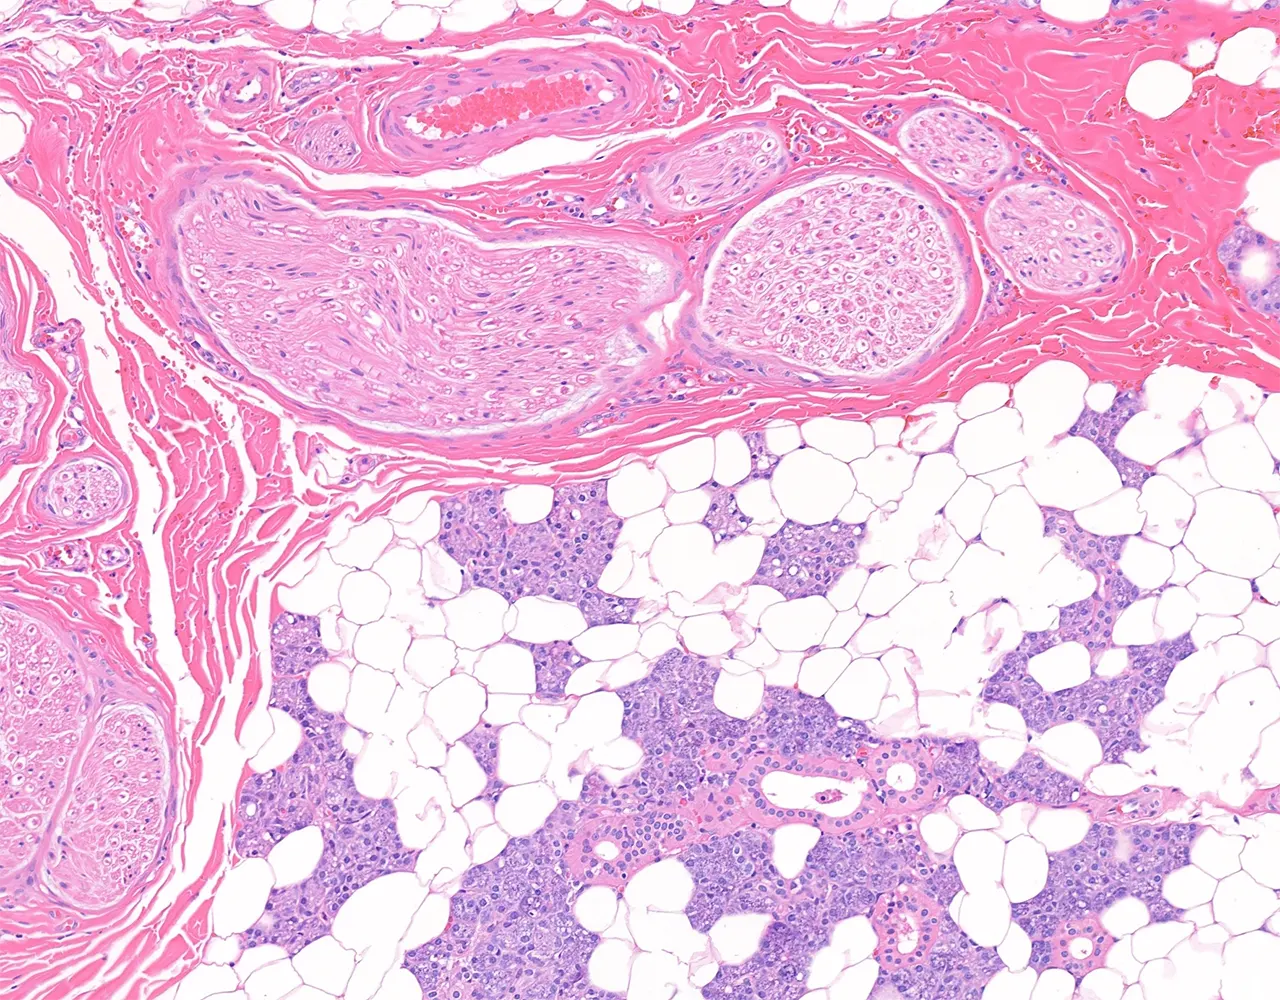

- Microscopically, the functional structure of a salivary gland consists of secretory acini and a duct system.